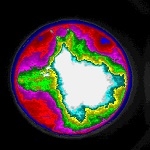

| 支援実績 | ●モノクロ/カラー画像の濃度、輝度、濃淡ムラ、発光解析等 ●色、濃度の面積解析 ●血流解析 ●眼球運動解析 ●液滴の落下速度解析 ●河川の流れ解析 ●地盤の変位歪み解析 ●口唇の変位解析 ●水理実験の流体解析、濃度ムラ解析 ●3次元動作解析 ●顕微鏡画像からの細胞周りの流体解析 ●虫、魚、小動物等の行動解析 ●CFRP断面解析 ●X線画像解析 ●医療画像解析 ●エコー画像解析 ●他多数 |